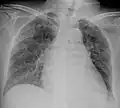

Tuberculosis of the lungs

Testing for miliary tuberculosis is conducted in a similar manner as for other forms of tuberculosis, although a number of tests must be conducted on a patient to confirm diagnosis.[3] Tests include chest x-ray, sputum culture, bronchoscopy, open lung biopsy, head CT/MRI, blood cultures, fundoscopy, and electrocardiography.[9] The tuberculosis (TB) blood test, also called an Interferon Gamma Release Assay or IGRA, is a way to diagnose latent TB. A variety of neurological complications have been noted in miliary tuberculosis patients—tuberculous meningitis and cerebral tuberculomas being the most frequent. However, a majority of patients improve following antituberculous treatment. Rarely lymphangitic spread of lung cancer could mimic miliary pattern of tuberculosis on regular chest X-ray. [14]

A case of miliary tuberculosis in an 82-year-old woman: